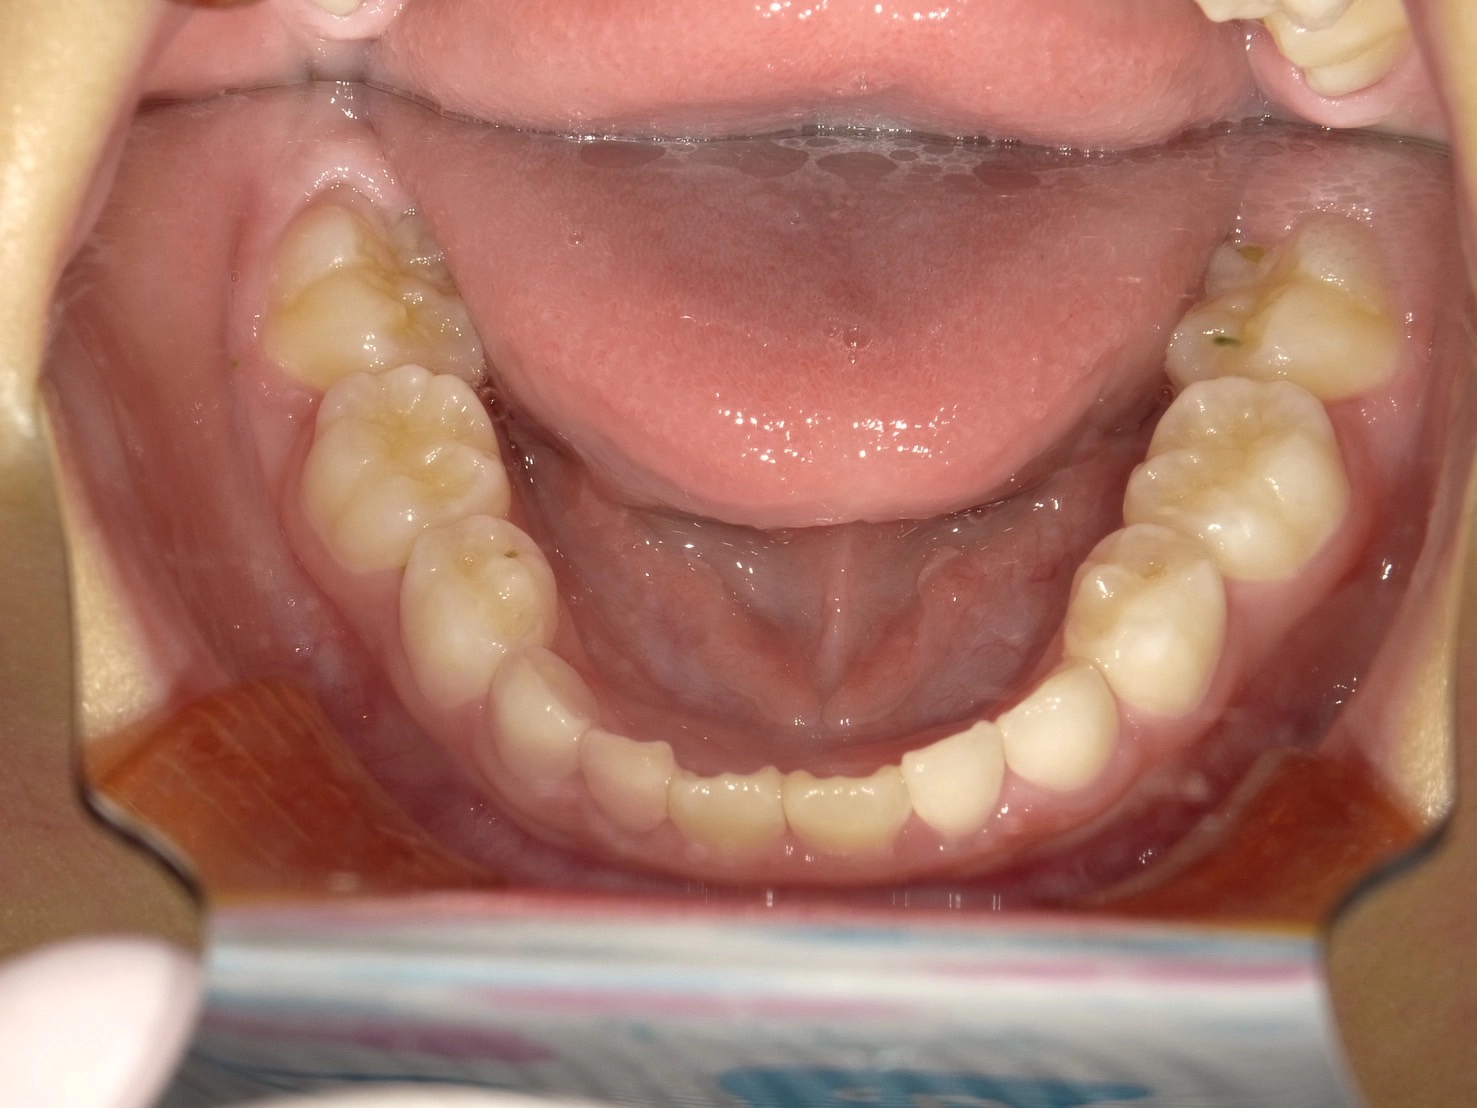

実際に小野歯科医院で行っているマイオブレースを用いた小児矯正の症例を紹介します。

どんどんきれいな歯並びになっていく様子を一緒に確認していきましょう!

治療前

術名 | マイオブレース矯正 |

---|---|

年齢 | 6歳 |

性別 | 男性 |

主訴 | 下の前歯のガタつきが気になる |

診断名 | 叢生 |

治療内容 | マイオブレース矯正 |

治療期間 | 治療開始2ヶ月時点での変化 |

費用 | 基本料33万(検査診断料.月々の調整料別途) |

リスク・副作用 | 特になし |

2か月後

4か月後

経過観察中…